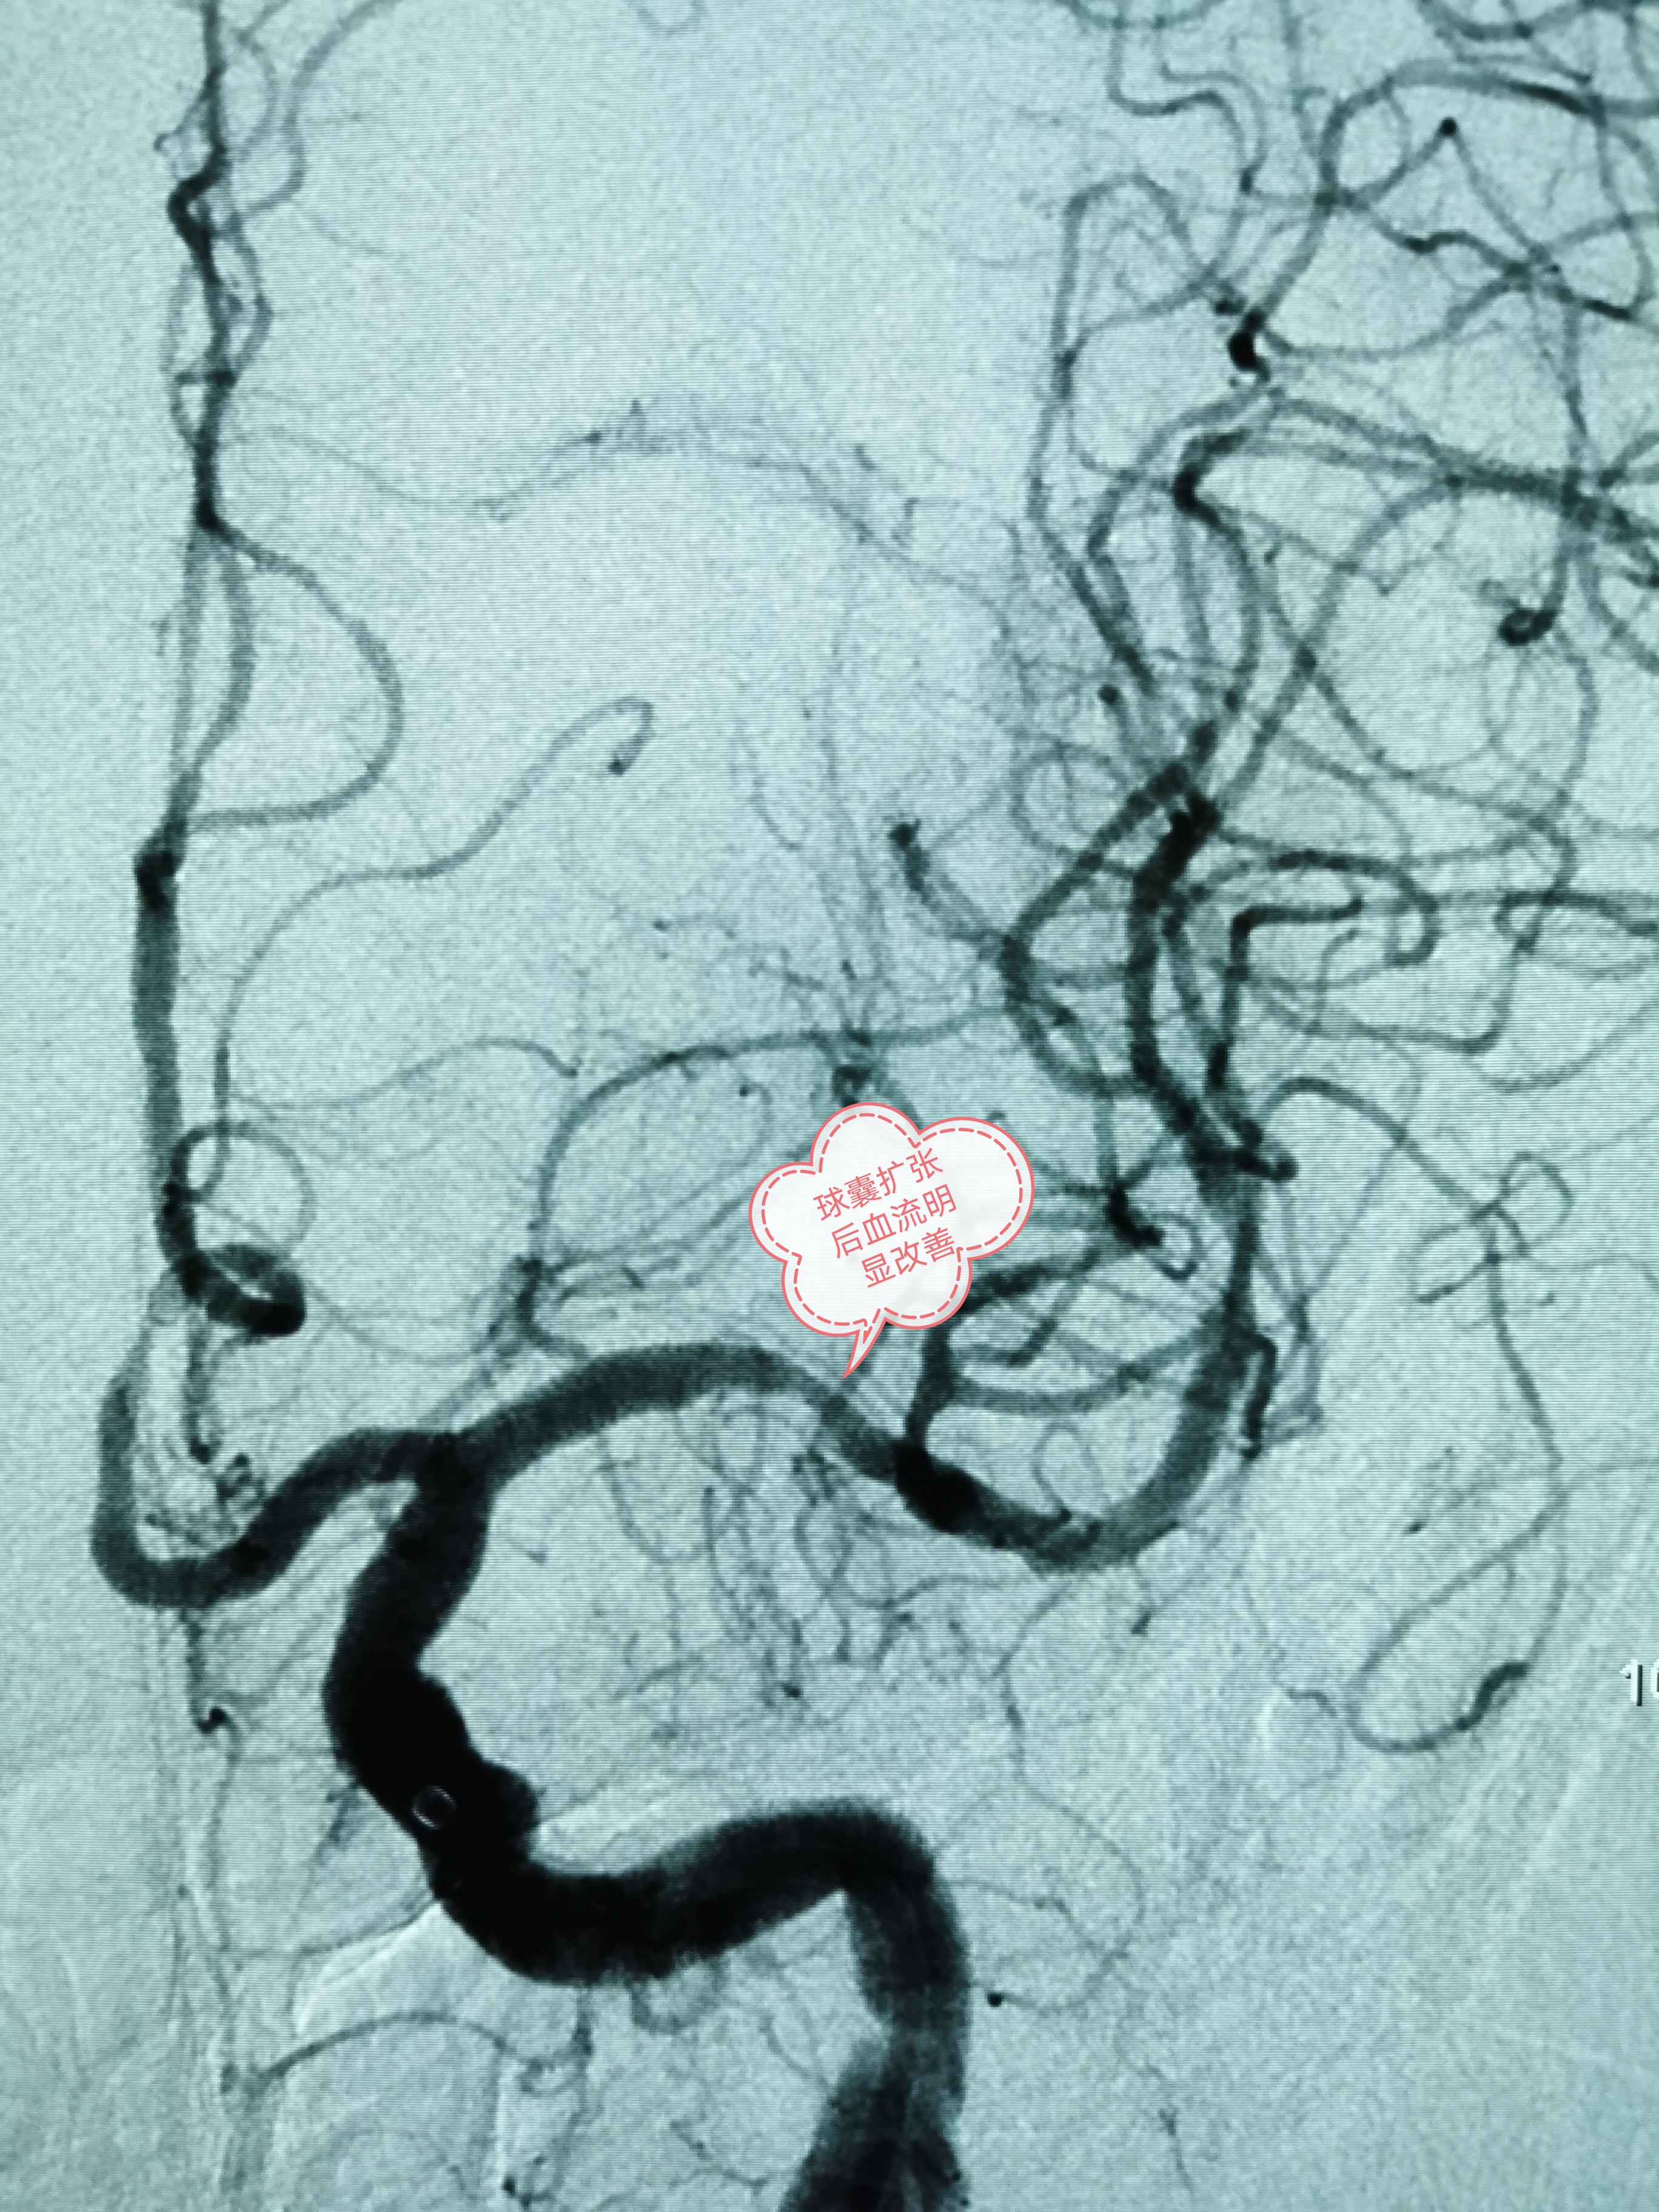

经过细致的术前准备后,班先生被送入介入导管室进行手术。术中发现班先生右侧颈内动脉一夹层动脉瘤,长14.4mm×高6.2mm,瘤颈宽10.8mm,合并左侧大脑中动脉重度狭窄。韦仕荣主任经过精细操作在患者右侧颈内动脉夹层动脉瘤处置入Tubridge血管重建装置,精确到位,即刻造影可见病变血管的血流形态明显改善。之后在左侧大脑中动脉重度狭窄处予球囊扩张成形术,造影显示血管狭窄明显改善,一次手术解决了两处重大的脑血管病变,手术过程顺利,且无并发症发生。次日班先生即可正常活动,恢复良好,术后第5天即康复出院。

球囊扩张后血流明显改善